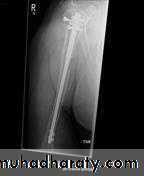

Operative treatment

Type of fixation either by plate and screws or intramedullary nail(in closed fracture) while in open fracture using external fixation with antibiotic cover, ATS and wound debridement and later on either secondary suture of the wound or skin graft in case of skin and soft tissue loss.